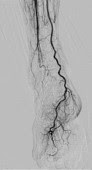

SCORE Chase*Aumenta a visibilidade de toda a área dos membros inferiores

A função SCORE Chase permite movimentos livres longitudinalmente ou lateralmente durante as exposições para rastrear o fluxo sanguíneo através dos vasos.